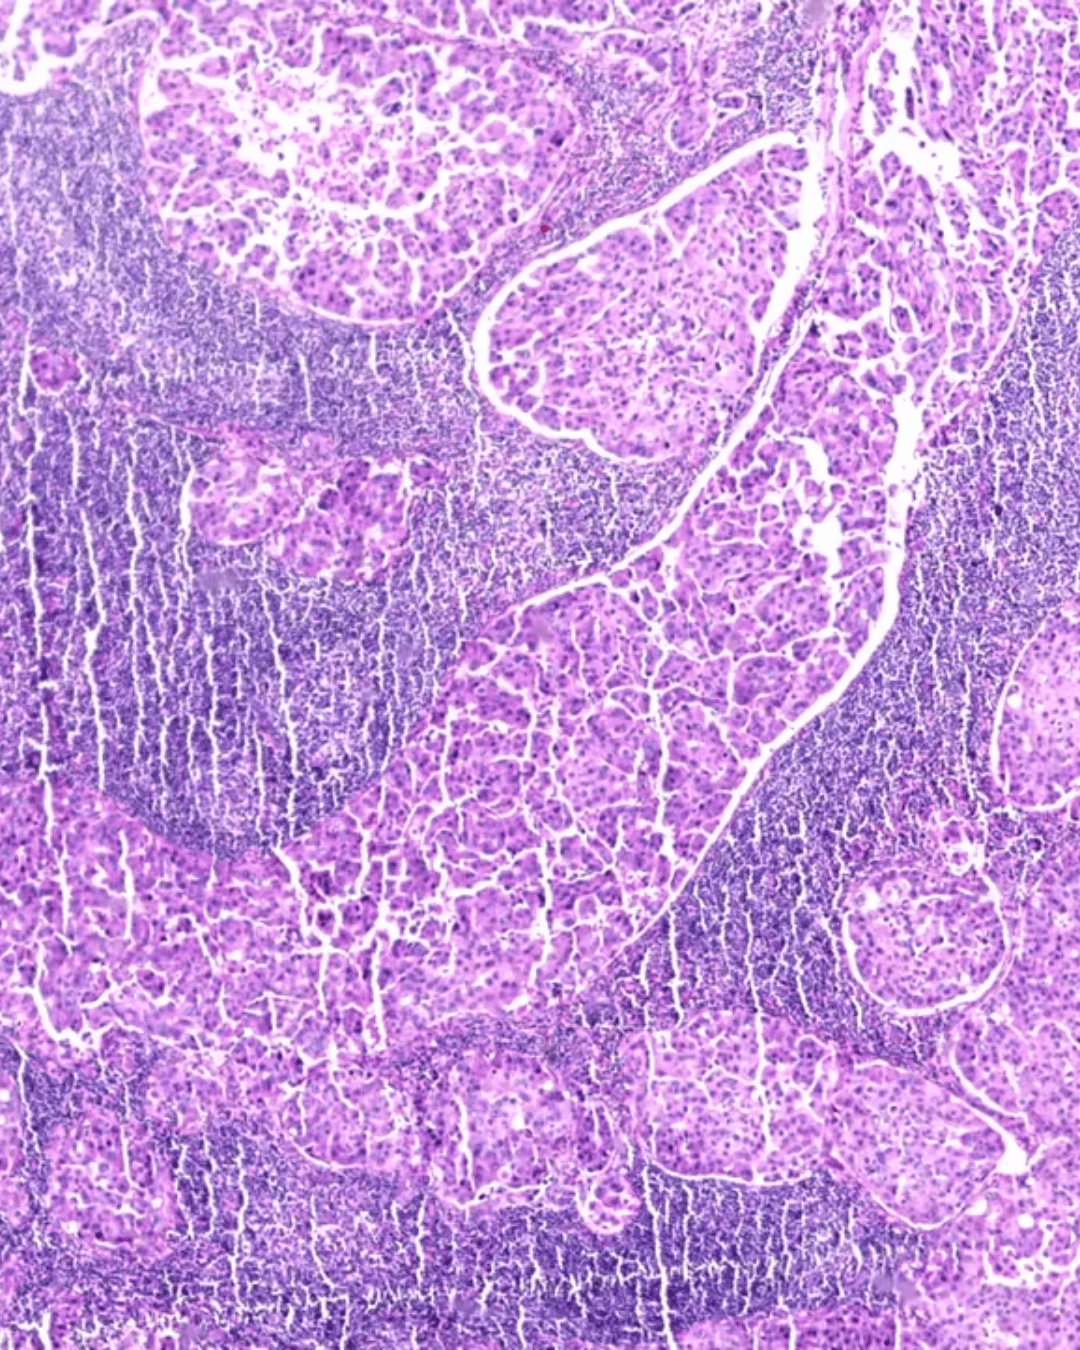

Lymph node under light microscopy

Lymph nodes are small, bean-like filters scattered throughout your body. They trap waste, dead cells, and harmful invaders like bacteria or viruses. Think of them as neighborhood watch stations—keeping tabs on what flows through your system and sounding the alarm when trouble shows up.